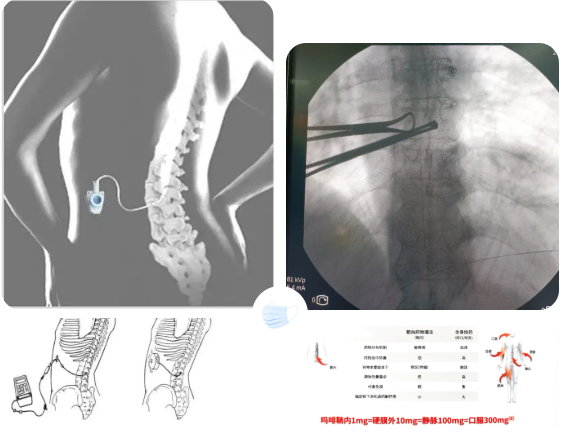

一、鞘内吗啡镇痛泵植入术

鞘内吗啡镇痛泵植入术,又称“植入式鞘内药物输注系统”,是一种先进的微创介入镇痛技术。它通过将药物直接输送到脊髓周围的脑脊液中,像建立一个“直达疼痛中枢的精准给药通道”,从而高效地控制顽固性疼痛。它真正实现了 “用最小的药量,达到最强的效果,产生最少的副作用”的精准医疗目标,为众多深受顽固性疼痛折磨的患者提供了重返高质量生活的希望,是“舒适化医疗”理念的杰出体现。是目前国际上治疗顽固性疼痛及癌痛的核心技术。

鞘内吗啡镇痛泵植入术优点:

2.精准靶向:鞘内给药只需要微小的镇痛药物的用量(相当于口服药物1/300)即可产生极大的镇痛效果。

鞘内吗啡本治疗示意图 鞘内吗啡泵相比传统给药方式剂量对比